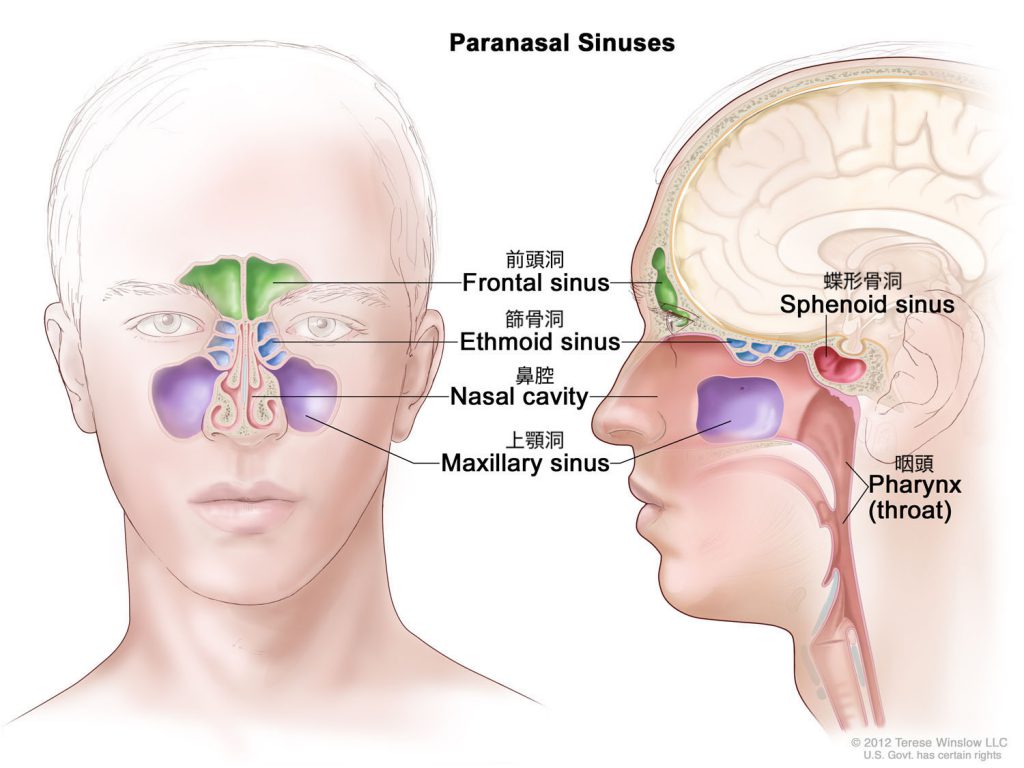

声帯振動は、喉頭や咽頭を通り口腔、鼻腔へ分岐し体外へ放出されます。この際、舌や口蓋などを動かし口腔の形状を変形させることで、「た」「け」「も」「と」等の言葉を発しています。一方、鼻腔や副鼻腔は骨と粘膜で形成されているので、その形状を動かすことができません。さらに、鼻副鼻腔は非常に複雑な形状をしており、個人差があります[1]。そのため、音声の個人性を生成する要因の一つであると言われています[2,3]。この鼻腔・副鼻腔を手術によって変形させてしまうと、音声の個人性が変化する可能性がありますが、その変化を予測する術はこれまでありませんでした。

模擬手術と音響シミュレーションによる鼻副鼻腔の音響特性の解明について、現在は副鼻腔の部位の1つである上顎洞の開放範囲(切除規模)の違いによる音声変化への影響の検討に取り組んでいます。本研究室では患者のCT(Computed Tomography)データから鼻副鼻腔を含めた声道形状を抽出し、抽出したデータを用いて手術(模擬手術)を行います。そのデータに対して音響シミュレーションを用いることで、手術後の音声変化を予測する手法を確立しました。この手法の確立によって実際に実験を行うことが難しい、開放範囲の違いによる音声変化の違いを検討することが可能となりました。

(緑:模擬手術による切除範囲)

- Dang et al., “Morphological and acoustical analysis of the nasal and the paranasal cavities”, JASA., 96(4), 2088-2100, 1994.

- Terese Winslow LLC, Medical And Scientific Illustration, Head And Neck, https://www.teresewinslow.com/#/head/ (閲覧日:2025/09/16)